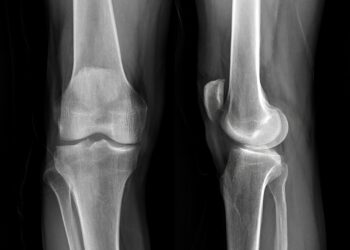

Skaityti daugiauDetailsOsgudo-Šlaterio liga – tai būklė, kuri dažniausiai pasireiškia vaikams ir paaugliams augimo šuolio metu, kai jų kelio girnelę prie blauzdikaulio...